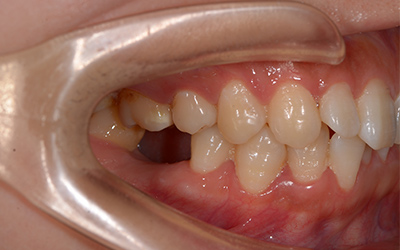

美牙后:牙成功修复,牙齿整齐洁白。

美牙技术:微数字化即刻种植牙